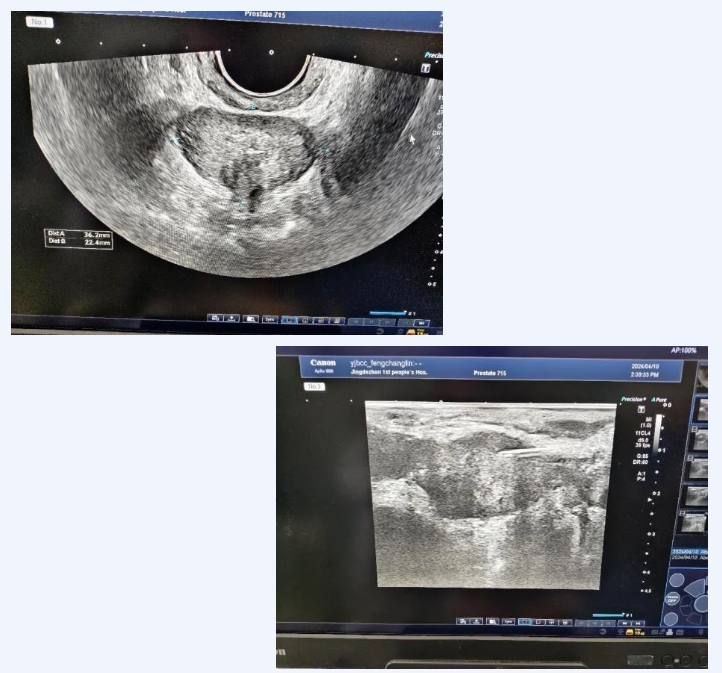

在接到任务后,超声医学科主任余健彬带领团队迎难而上,第一时间组织组内讨论,迅速制定出最佳方案,确定由余健彬为患者实施经会阴前列腺穿刺术。术中,余健彬在泌尿外科殷桂林的协助下,以沉稳娴熟的技术,将直肠引导探头置入直肠内,经会阴部以18G活检针分别对左右侧内外腺前、中、后各取材1针,准确地获取前列腺12条约为2厘米的组织样本。穿刺过程及穿刺后,患者均无表达不适,术后复查针道无出血。